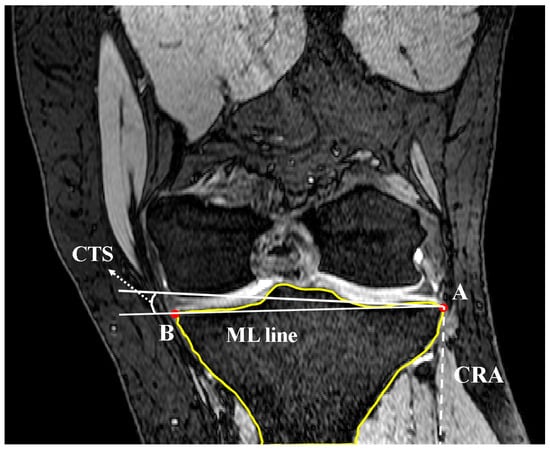

2.2. Coronal Tibial Slope Measurement Method

2.3. Concavity Zone